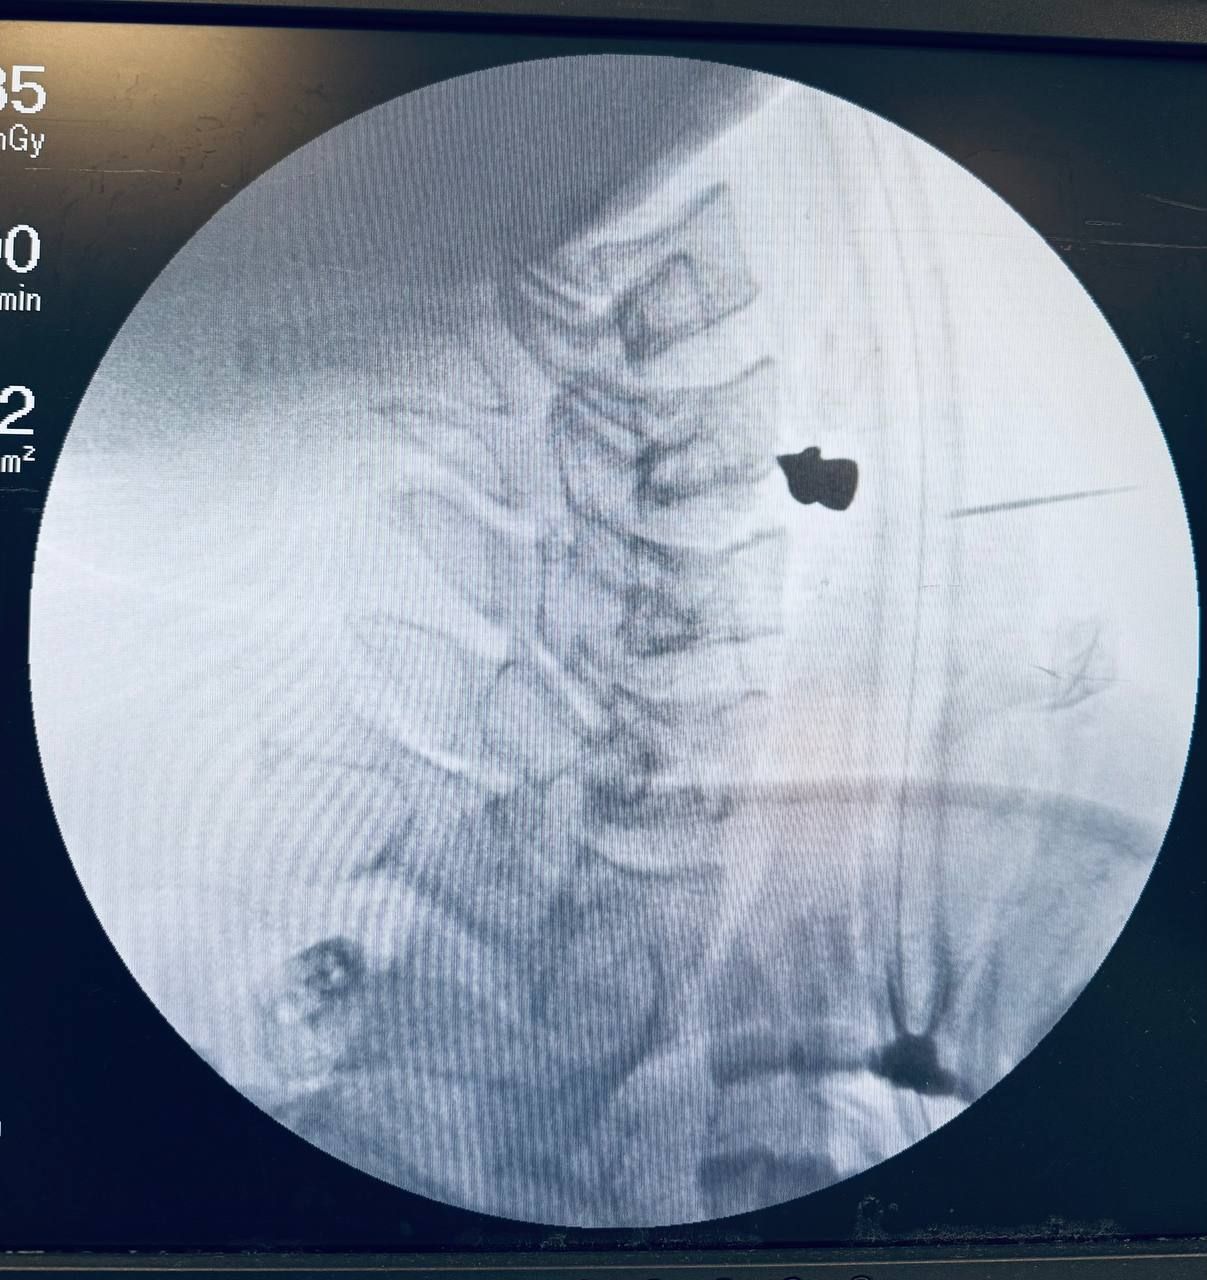

Случайный выстрел: в Татарстане мужчине удалили пулю, застрявшую в позвоночнике

Она чудом не задела жизненно важные органы

В Татарстане 25-летнему жителю Зеленодольского района удалили пулю из шеи после неосторожного обращения с пневматическим ружьём. Молодой человек случайно выстрелил в себя во время разборки оружия.

Как рассказал пострадавший, он не заметил, как сработал механизм, и лишь почувствовал, как из шеи хлынула кровь. Друзья сразу доставили его в центральную районную больницу, откуда пациента перевели в Республиканскую клиническую больницу Казани.

Обследование показало, что пуля чудом не задела жизненно важные органы — артерию, трахею и пищевод, но остановилась в позвоночнике. Мужчина испытывал трудности с глотанием и речью.

Операцию по извлечению пули провели заведующий ЛОР-отделением Марат Гилялов и заведующий отделением нейрохирургии Георгий Майков. Хирурги справились всего за 20 минут, после чего наложили швы на рану.

Сейчас пациент находится в палате и проходит восстановление.

Фото: РКБ